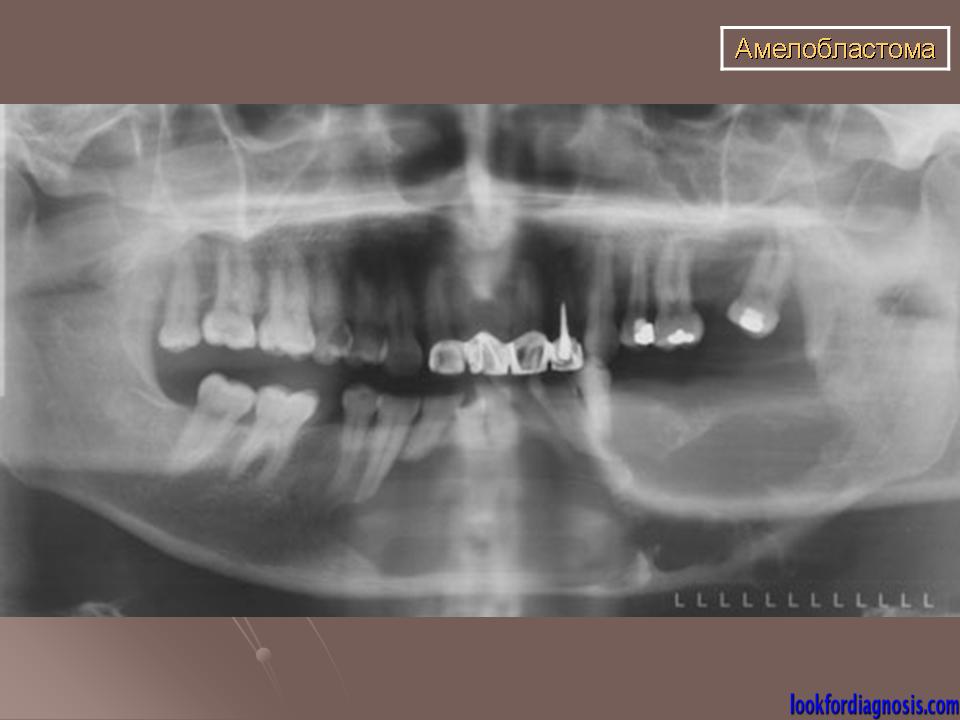

Амелобластома - доброкачественная одонтогенная эпителиальная опухоль, способная к инвазивному росту. Развивается внутри кости, по микроструктуре напоминает стадии развития эмалевого органа, наблюдается чаще у лиц среднего возраста, в 80% случаев поражает тело нижней челюсти в области моляров и премоляров, а также угол и ветвь нижней челюсти. Редко она обнаруживается в области резцов. Проявляется чаще в возрасте 20-50 лет с одинаковой частотой у лиц обоего полу, может встречаться и у детей.

• OPG & # 160;